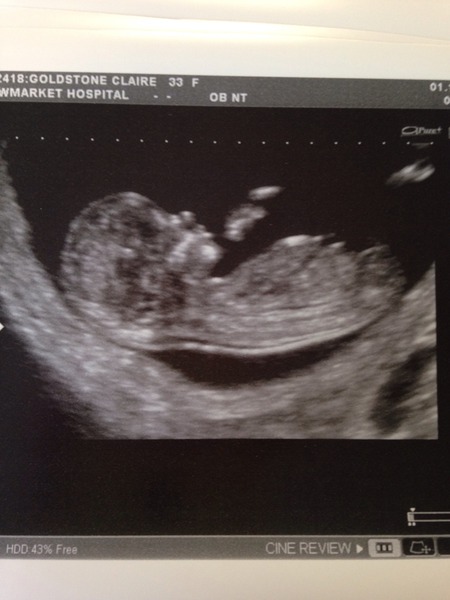

Another one putting her name down for a personal ultrasound, please